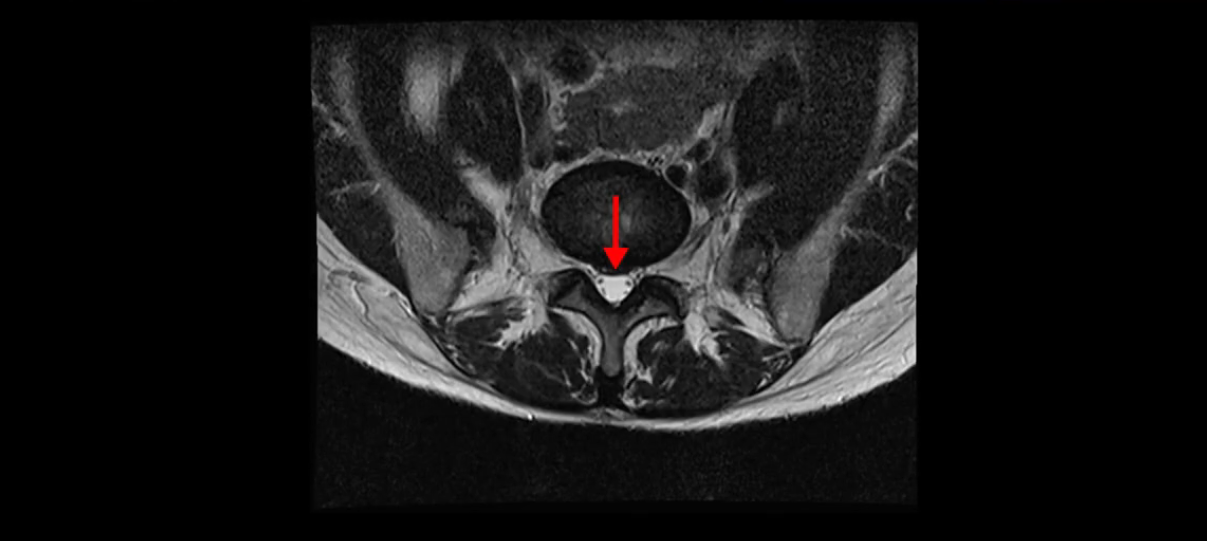

우선 이분의 MRI를 보고 먼저 설명을 드린 후 이런 환자분들의 통증의 원인은 무엇인지, 그리고 치료는 어떻게 해야 하는지 자세히 설명 드리겠습니다.

이분 MRI를 보시면 두 마디의 퇴행성디스크가 있습니다. 그리고 디스크가 조금씩 밀려 나와 있고요. 그런데 디스크 탈출 정도는 두 마디 다 심하지 않습니다. 4번 5번에는 디스크 탈출이 약간 있고,

척추관협착도 약간 진행이 되고 있고요.

5번 1번은 디스크 탈출이 가운데 쪽으로 살짝 있습니다.

또한 양쪽 신경 가지가 빠져나가는 추간공은 매우 넓은 상태입니다.

중요한 것은 이 정도 경미한 탈출과 협착으로는 양쪽 다리가 저리고 아플 수가 없습니다.

그리고 만약에 이 디스크가 급성으로 찢어진 것이라면 아주 심한 디스크성 통증이 있겠죠. 기침이나 재채기를 하면 심하게 아프고 허리를 조금만 구부려도 아주 날카로운 통증들이 생길 겁니다. 그런데 이분은 이런 증상이 전혀 아닙니다. 디스크의 돌출 정도와 협착이 전혀 심하지 않기 때문에 이분이 가지고 계신 양쪽 다리 저림, 특히 이분은 누워있을 때도 양쪽 다리가 저리다고 하는데, 디스크 때문에 그런 증상은 생길 수가 없습니다. 또 이 디스크는 오래된 디스크, 이미 찢어진 섬유륜이 아문 디스크이고, 그러니까 이분은 기침이나 재채기를 못하는 증상이 없는 거죠. 그 다음에 허리를 구부릴 때 뻐근한 증상은 있지만 아주 날카로운 통증은 없습니다.

이분 MRI를 보시면 퇴행성디스크가 있고 약간의 협착이 있지만 이 정도의 퇴행성디스크와 협착으로는 신경이 눌려서 양쪽 다리가 저리고 아픈 증상이 나올 수가 없습니다. 그래서 MRI와 이 환자분의 다리 증상이 매치가 안 된다고 하는 의사들이 많은 겁니다.